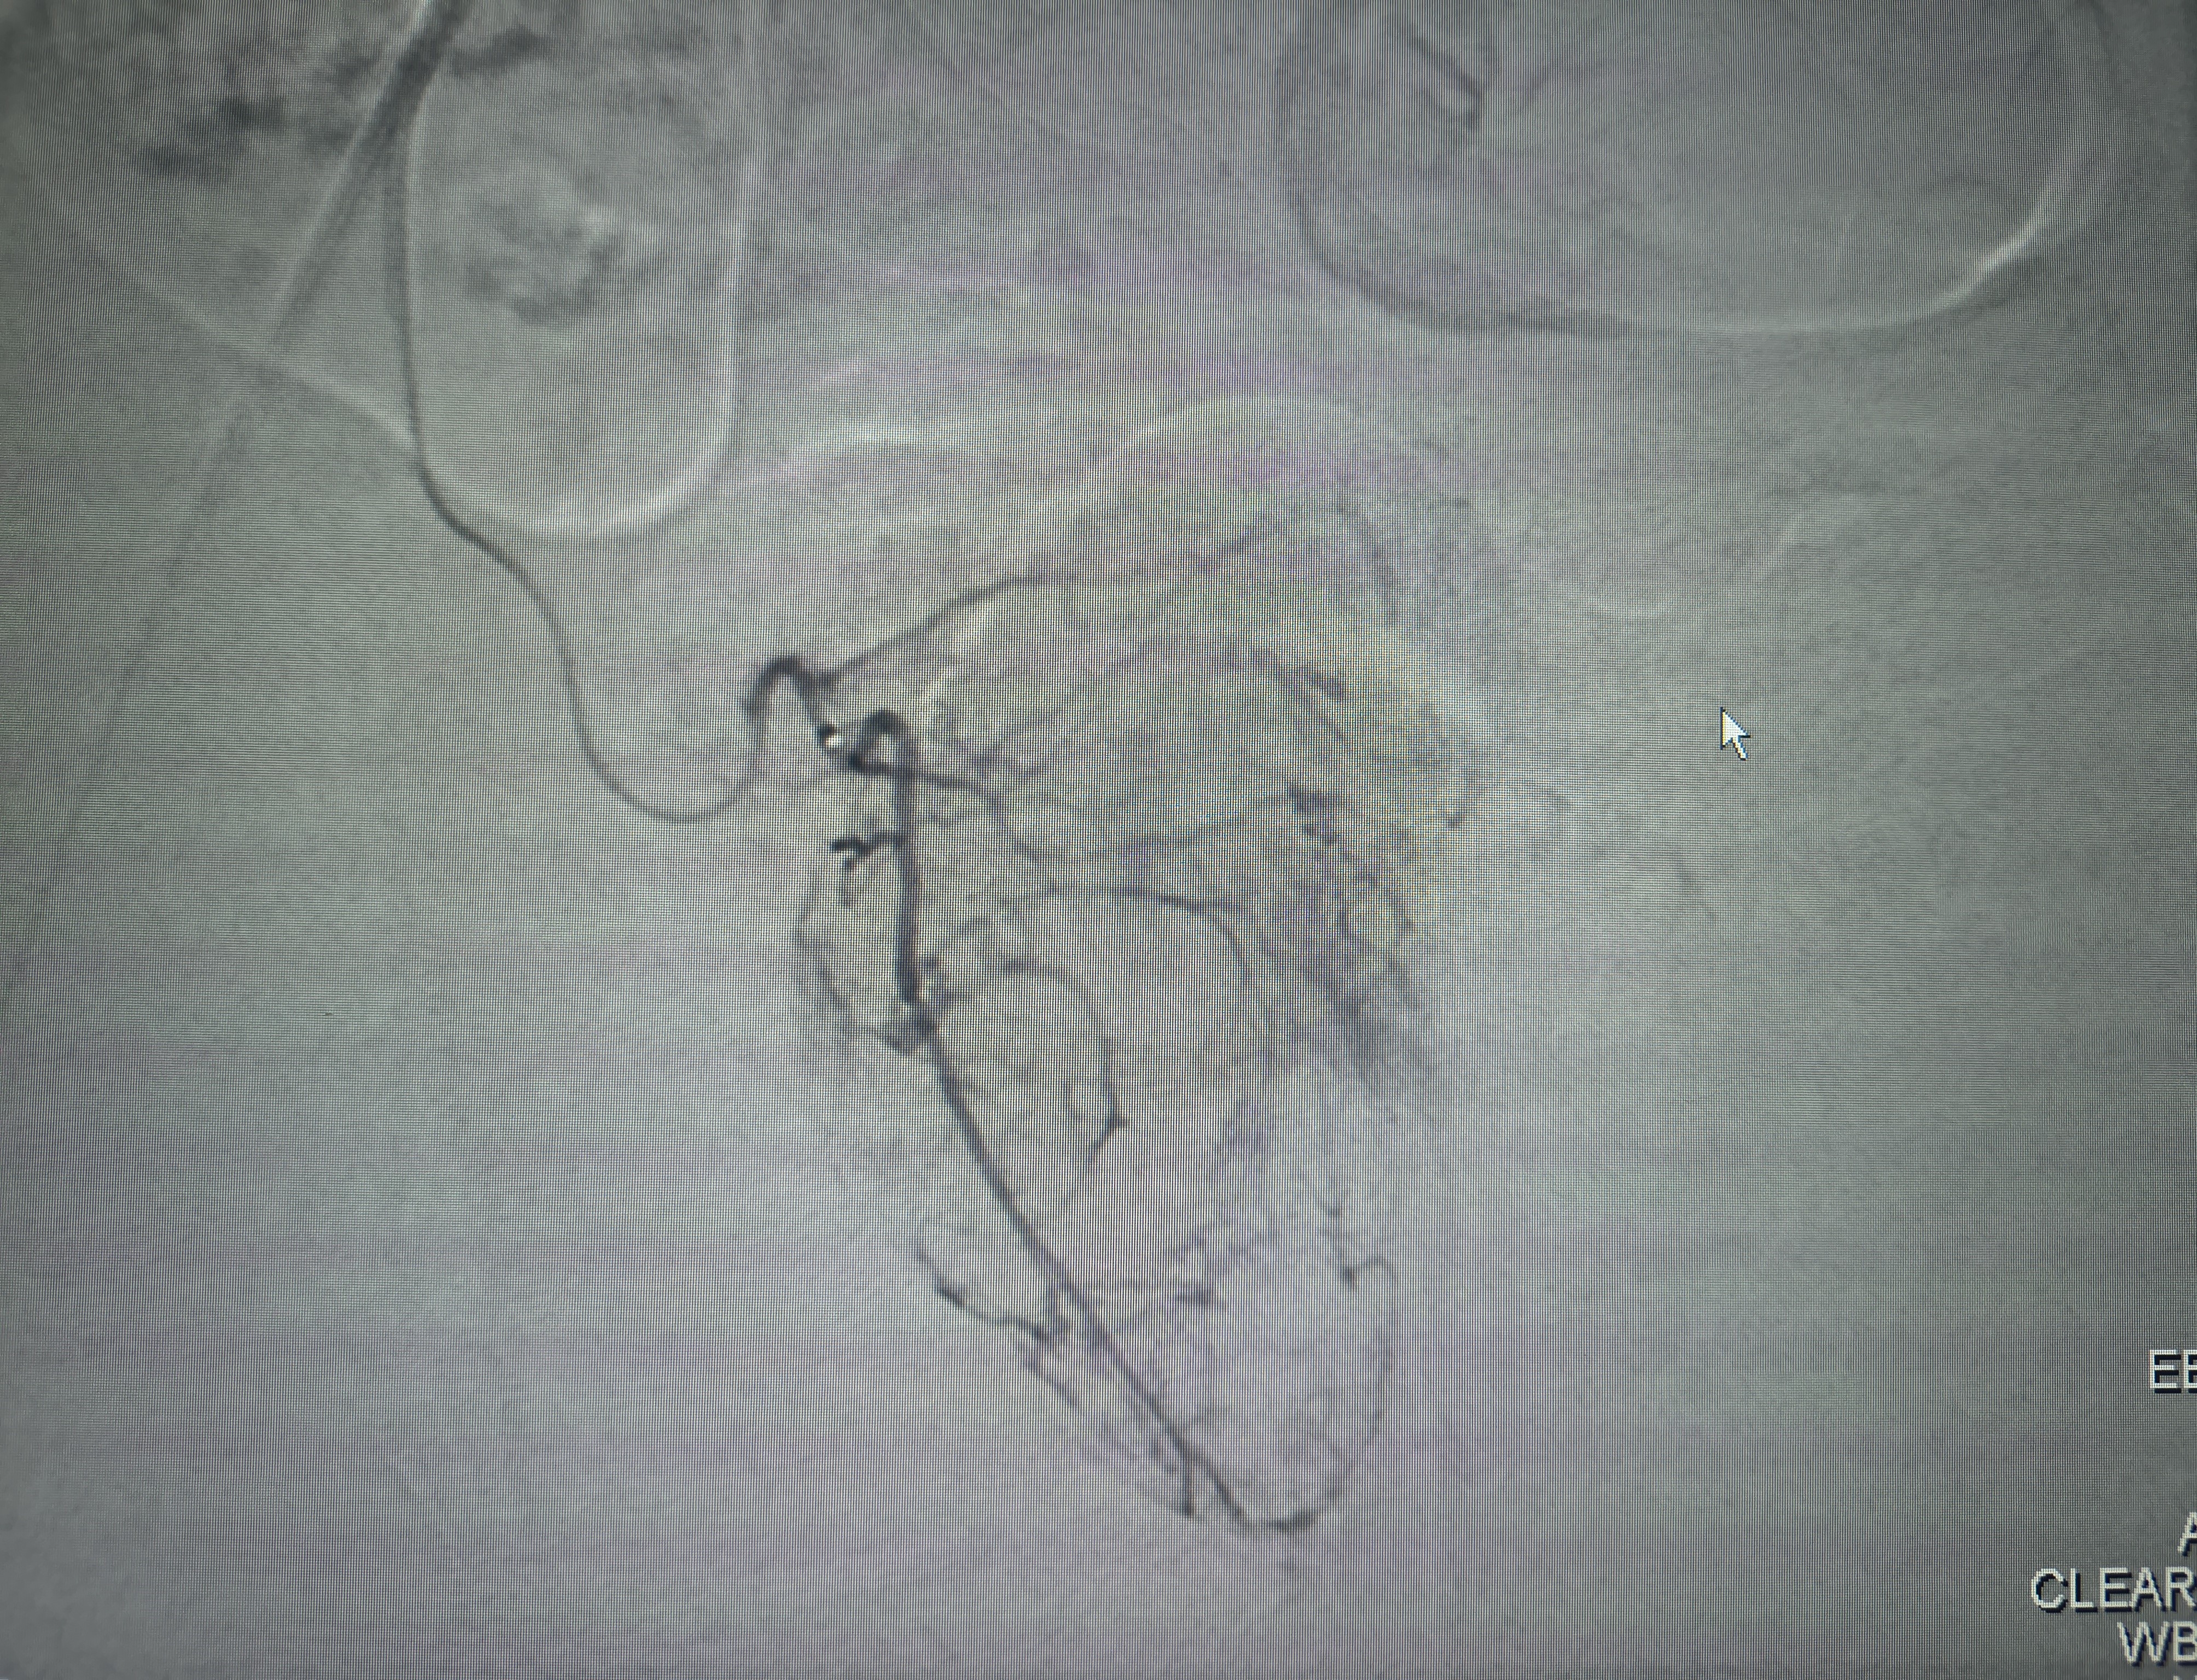

Prostate Artery Embolization